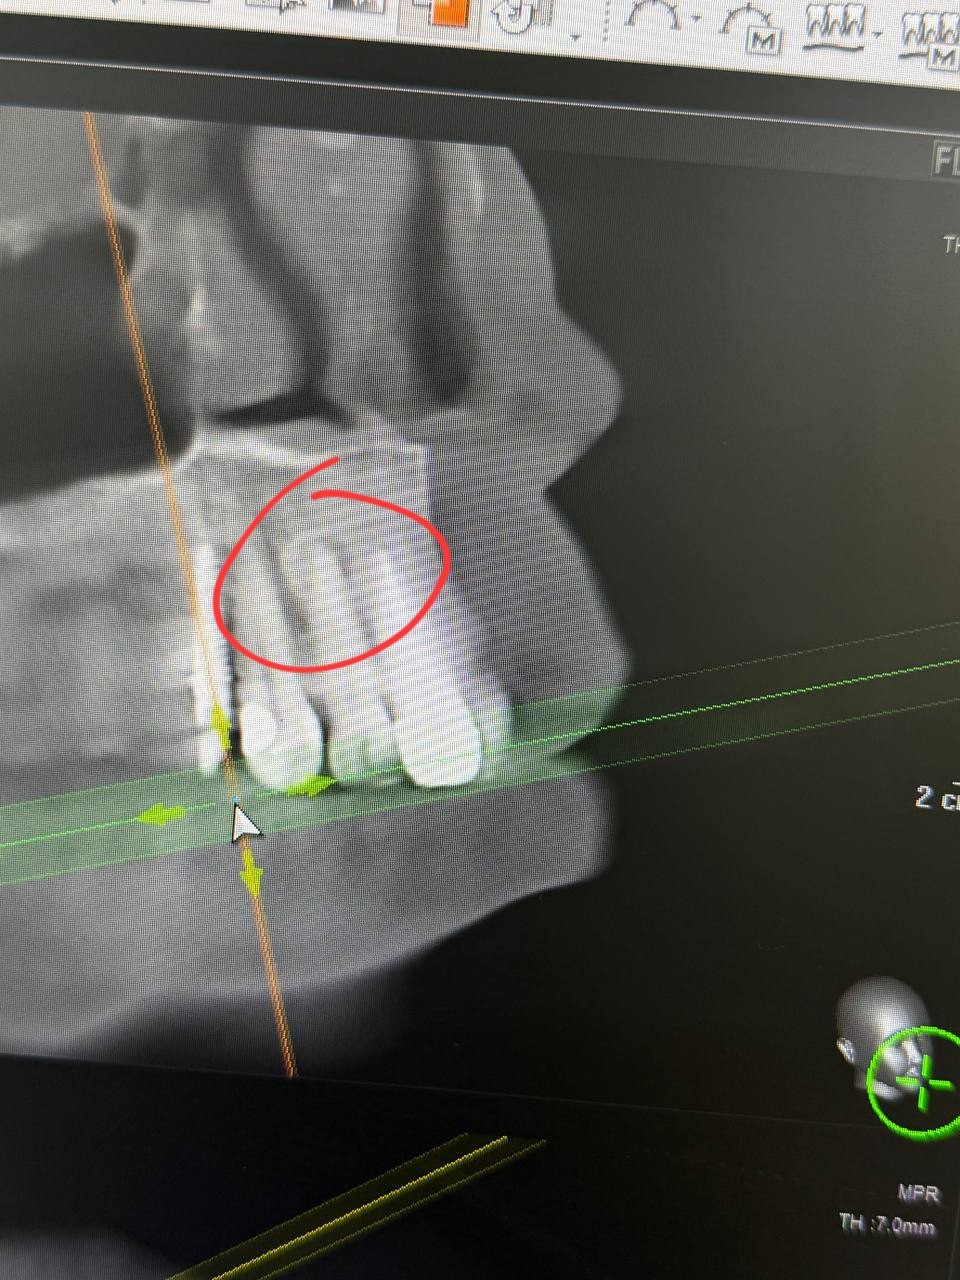

Здравствуйте, прохожу протезирование коренных зубов. КТ показало образование на корнях зубов 12 и 43. Врач затрудняется ответить что это может быть.

В нижнем отделе вдоль всех зубов идёт прерывистое образование. Всё одонтома? И какие дальше должны быть действия? Протезировать можно при такой патологии? Удалять? Гистолгия? Тактика?

Мой лечащий врач склонен считать что это цементно костная дисплазия и в верху и внизу. Предлагает не трогать и смотреть в динамике как образование будет себя вести в дальнейшем (это вверх). Низ просто под наблюдением, там коронок не будет. Если будет рост на корне 12, возможна резекция корня с последующей гистологией. Как бы решать проблему по мере поступления.